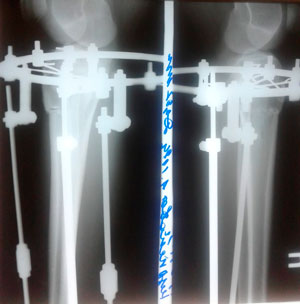

Дата операции - 29.04.2019г.